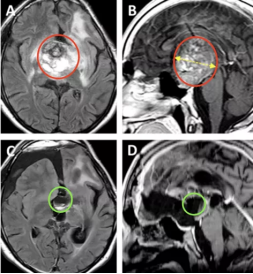

图A、B为术前MRI影像。

图C、D显示为几乎全切的术后MRI